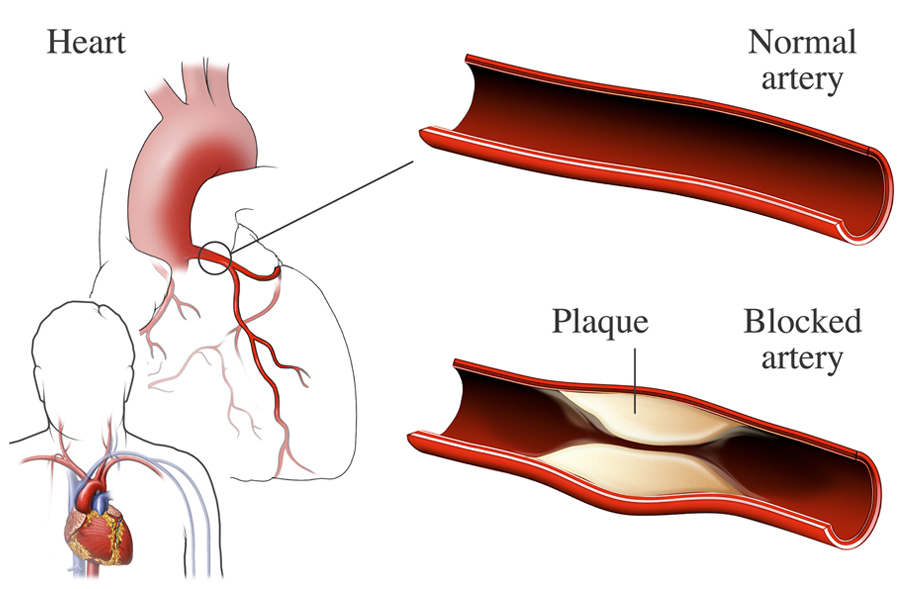

Can A Blockage Cause Irregular Heartbeat

Can A Blockage Cause Irregular Heartbeat

Nursing Awareness Nursing Exam Notes Nursing Quizzes Nursing Old

https://www.nhlbi.nih.gov/sites/default/files/inline-images/ischemic-heart-disease_arteries.jpg